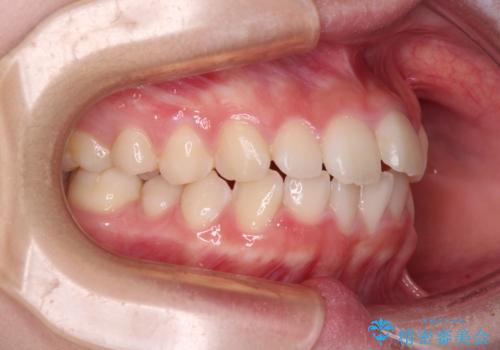

- 前歯のデコボコを気にして来院された高校生の患者様です。

捻れた前歯が前方に飛び出している点も気になっており、目立たない装置を希望されたため、インビザラインを用いて矯正治療を行うこととしました。

上下ともに少し捻れが残っていたため、治療の継続を提案しましたが、本人も親御さんも満足とのことで、治療を終えました。

捻れの改善により突出感も改善されました。